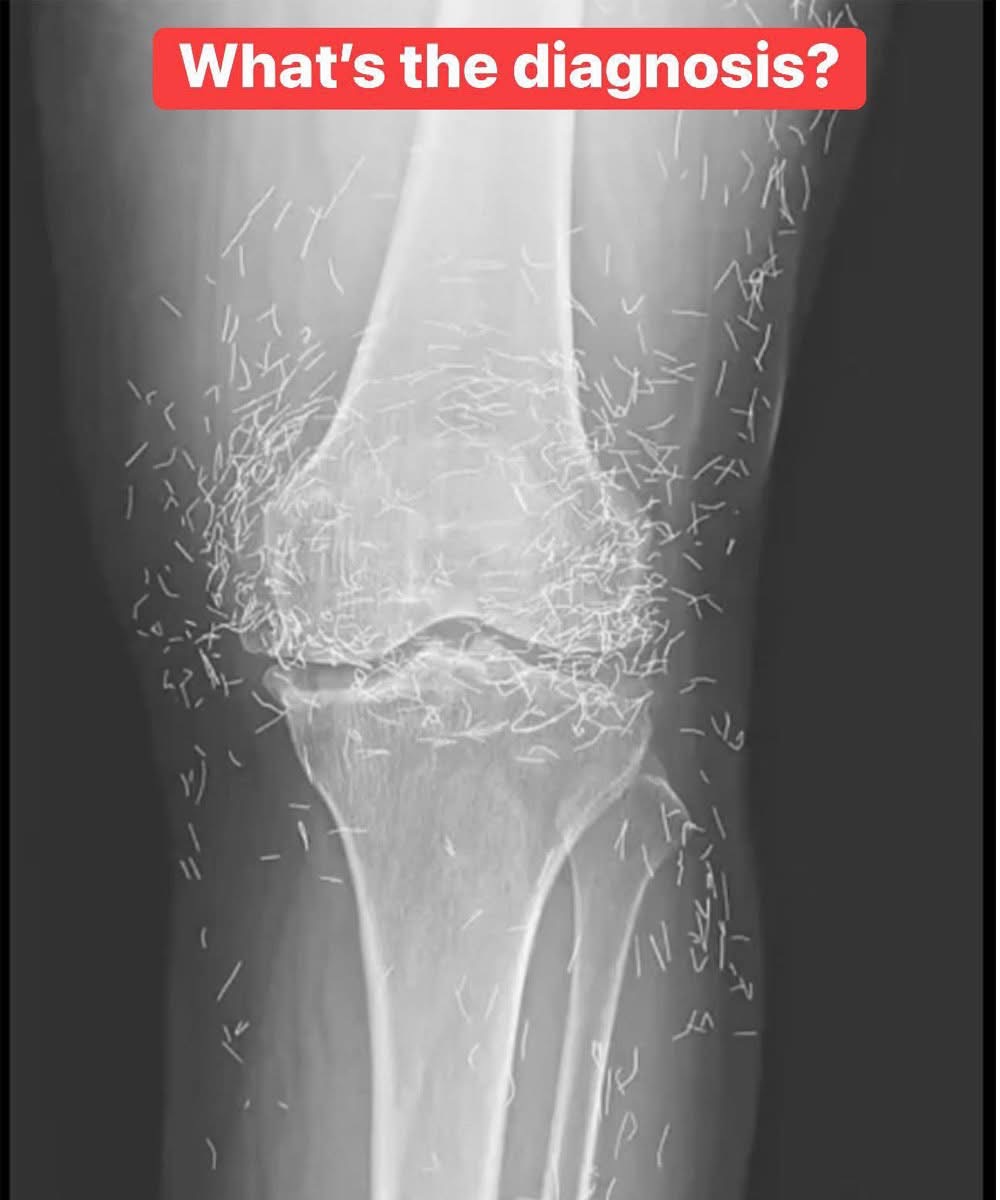

The 65-year-old woman from South Korea had previously been diagnosed with osteoarthritis, a condition in which the cartilage and bones within the joints degrade, causing pain and stiffness. However, when pain relievers and anti-inflammatory drugs didn’t alleviate the pain in her knees and only caused stomach discomfort, she had turned to acupuncture, the doctors wrote last week in the New England Journal of Medicine.

Acupuncture is an alternative medical practice that uses needles in order to purportedly stimulate certain points on the body, to alleviate pain or to treat a variety of diseases.